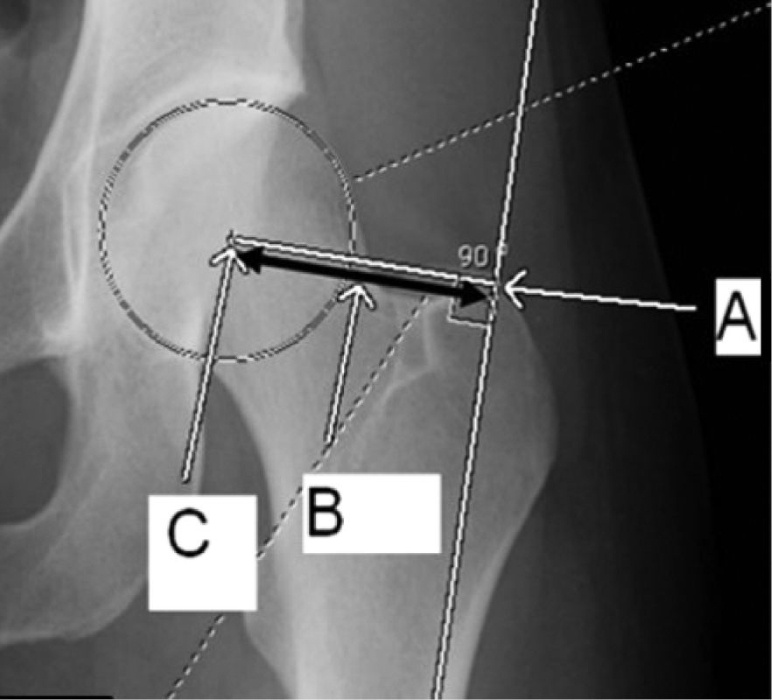

Postoperative evaluation included immediate anteroposterior (AP) and lateral X-rays of the hip. The femoral NSA was determined according to the methodology described by C. K. Boese et al. [10]. This angle was calculated between the axis of the femoral neck and the anatomical axis of the FS. The neck axis was drawn from the femoral head center (HC) to the neck center (NC), the latter defined as the midpoint between points where a circle (centered on the HC) intersected the superior and inferior borders of the femoral neck. The shaft axis was established by connecting central points identified at both proximal and distal segments of the femoral diaphysis [11]. The tip-apex distance (TAD) was calculated as the cumulative length from the screw tip to the apex of the femoral head as seen on both the AP and lateral projections [12]. FS lateralization was assessed by measuring the horizontal distance from the femoral head center to a reference line parallel to the lateral cortex of the femur, comparing the injured side with the contralateral uninjured side [7] (Figures 1, 2).

Figure 2. Calculation of the wedge effect (net lateralization of the shaft compared to the head/neck segment): line B represents the distance from the center of the femoral head (C) to the lateral femoral shaft (A)